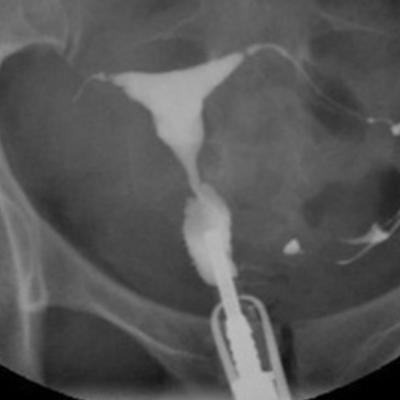

子宮卵管造影(hysterosalpingography:HSG)は、造影剤を子宮腔内に注入し、子宮内腔、卵管の陰影から子宮腔の状態、卵管の疎通性および骨盤腔内の癒着を判定する検査です。

リピオドール®の臨床成績(子宮卵管撮影)

方法:月経終了後4、5日に造影剤としてリピオドール®480注10mLを使用し、子宮卵管造影を実施した。

総症例1,050例において本剤の造影能に良好な成績が得られました。